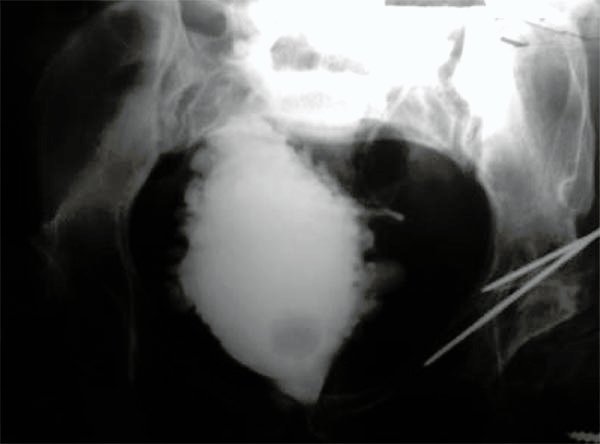

Paciente de sexo femenino de 34 años de edad con MMC Grado 3. Defecto del tubo neural corregido a las 6 horas de vida e hidrocefalia tratada con una derivación ventriculoperitoneal a los 12 meses de vida. No efectuaba cateterismo. Urograma excretor: normal. Incontinencia fecal y urinaria. Siempre uso pañales. A los 22 años de edad se realizó cistografía retrógrada con resultado patológico (fig. 2).

Figura 2:

Cistografía paciente n°3.